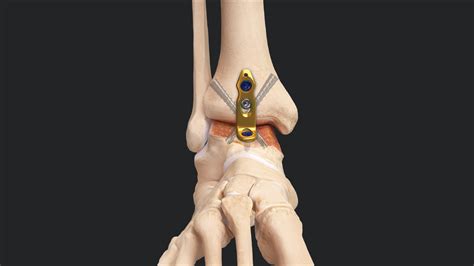

Ankle Fusion Procedures work by removing the damaged cartilage from the joint surfaces of the talus (the top bone of the foot) and the tibia (the shin bone). Once the cartilage is removed, the surgeon uses metal hardware, such as plates, screws, or rods, to hold these two bones together in a fixed position. Over the course of several months, the body naturally heals by bridging these bones with new bone tissue, creating a single, solid bone structure. The primary goal is to eliminate pain by preventing the grinding of bone-on-bone that occurs in advanced arthritis.